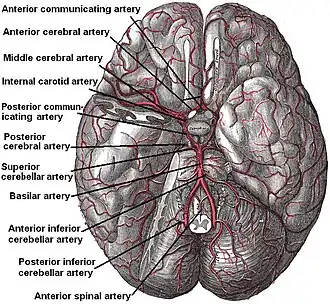

The basilar artery (middle of figure) arises from the vertebral arteries and terminates when it bifurcates in the left and right posterior cerebral arteries. | |

The arteries of the base of the brain. Basilar artery labeled below center. The temporal pole of the cerebrum and a portion of the cerebellar hemisphere have been removed on the right side. Inferior aspect (viewed from below). | |

Артерия отдает ветви к мосту и мозжечку, таламусу, височным долям коры больших полушарий головного мозга, продолжается двумя задними мозговыми артериями.